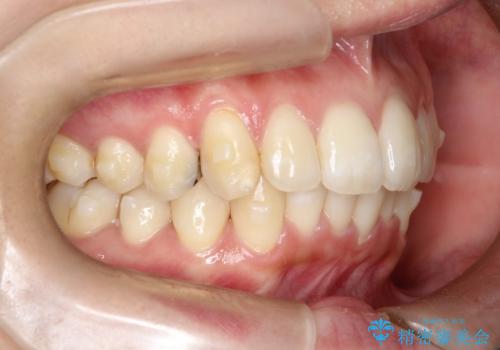

- 前歯のでこぼこが気になると来院されました。

奥歯の噛み合わせは綺麗に噛んでいたため、前歯の叢生(でこぼこ)を、短期間で治療完了するように計画しました。

奥歯の噛み合わせは整っていたため、前歯の並びを美しく修正することに専念できました。マウスピース矯正による治療で短期間で改善しました。